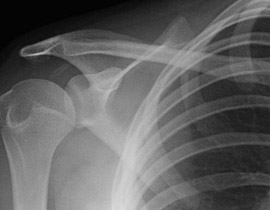

تعاني شابة بريطانية في العشرين من العمر من أعراض تجعلها تخلع كتفها كلما عطست بصورة مفاجئة، وتذهب إلى المستشفى لإعادة كتفها المخلوع إلى مكانه الطبيعي. إن "لورين هاري" تعاني من ألم شديد بعد العطس، الذي يمكن أن يحدث لها 20 مرة يومياً في أسوأ الحالات، بعد السعال، أو التعثّر، أو أدنى هزة عند قيادة سيارتها.

وقالت صحيفة "ديلي ميرور": أن الأطباء يعتقدون أن: "لورين" تعاني من أعراض (إهلرز دانلوس)، وهي حالة وراثية تعني أن مادة الكولاجين البروتينية في عظامها ضعيفة جداً، للحفاظ على أطرافها في مكانها الطبيعي. وأشارت الصحيفة إلى أن الشابة البريطانية راجعت المستشفى 4 مرات في الأسبوع الماضي فقط للعلاج، بعد أن خلعت عطساتها كتفها، وعانت للمرة الأولى من أعراض "إهلرز دانلوس" في ساقيها حين كان عمرها 11 عاماً.

وقالت: إن "لورين" وقعت على الأرض بعد 4 سنوات، ما أدّى إلى إصابة كتفها، وصارت تعاني منذ ذلك الوقت من خلع منتظم في مفاصلها، بما في ذلك خلع الركبتين، وأصابع اليدين.